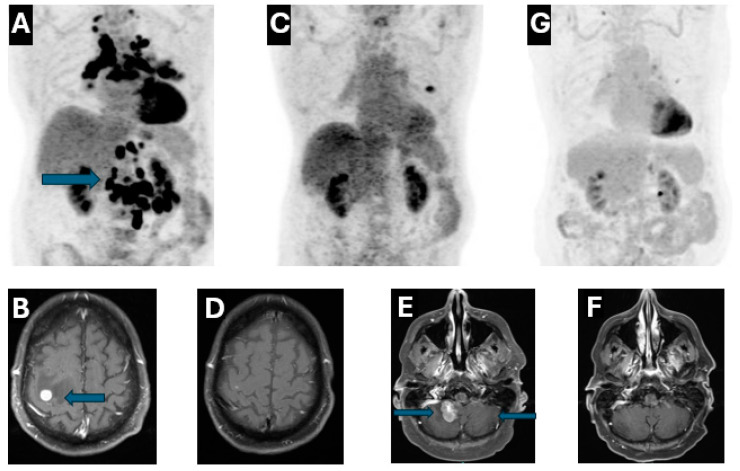

Background and Clinical Significance: The mesenchymal-epithelial transition (MET) exon 14 skipping mutation (METex14) is a rare genetic alteration occurring in non-small cell lung cancer (NSCLC). Tyrosine kinase inhibitors (TKIs) are the approved treatment for first-line therapy in a metastatic setting. However, the unusual presentation of gastrointestinal metastasis and leptomeningeal carcinomatosis (LMD) poses significant treatment challenges. Case Presentation: Here we report a case of a 72-year-old male with metastatic METex14-positive NSCLC, presenting with brain and duodenal metastases. Conclusions: The patient responded exceptionally well to first-line chemoimmunotherapy, achieving clinically complete remission for 2 years. He subsequently developed cerebellar metastasis and leptomeningeal disease (LMD) but demonstrated a remarkable response to tepotinib and continued to enjoy radiographic complete remission over 2.5 years at the time of this report.